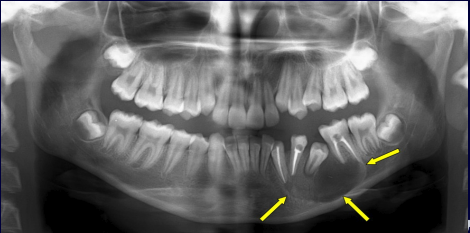

What are the 7 signs of IAN involvement?

1.Darkening of the roots 2.Interruption of the white line 3.Diversion of the mandibular canal 4.Deflection of the roots 5.Narrowing of the roots 6.Dark and bifid roots 7.Narrowing of mandibular canal